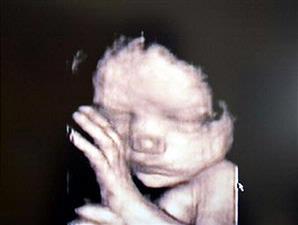

Citra janin bayi dalam kandungan melalui alat ultrasound tiga dimensi.

Dibandingkan USG dua dimensi (2D), tentu saja teknologi 3D dan 4D lebih maju. Melalui USG 3D, gambar janin dapat dilihat secara utuh, seolah-olah melihatnya secara langsung. Pada USG 4D, kita bahkan bisa melihat gerakan seperti gerakan jari, kepala, hingga denyut jantung janin.